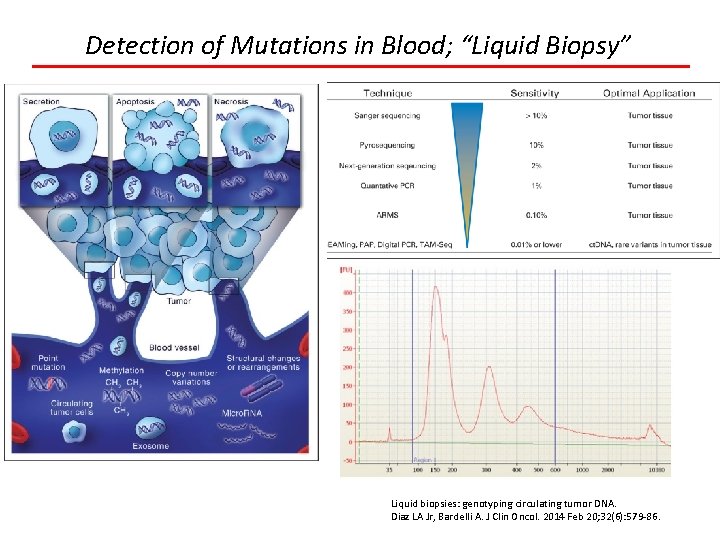

Detection of Mutations in Blood; “Liquid Biopsy” Liquid biopsies: genotyping circulating tumor DNA. Diaz LA Jr, Bardelli A. J Clin Oncol. 2014 Feb 20; 32(6): 579 -86.

Detection of Mutations in Blood; “Liquid Biopsy” Applications Minimal residual disease Resistance mutations Initial genotyping when no tissue available Early detection/screening Research of heterogeneity Liquid biopsies: genotyping circulating tumor DNA. Diaz LA Jr, Bardelli A. J Clin Oncol. 2014 Feb 20; 32(6): 579 -86.